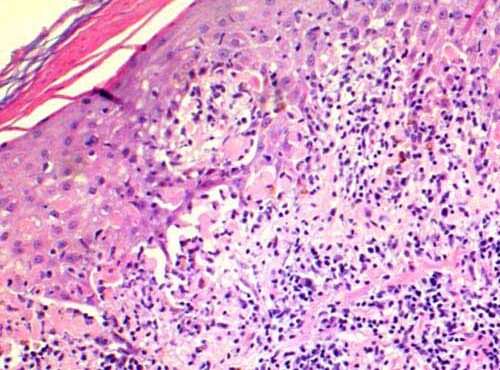

BCC with squamous differentiation =الورم القاعدي الخلايا مع تمايز شائك